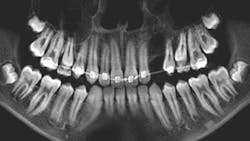

Patient: 14-year-old female entering orthodontics

- Congenitally missing teeth nos. 17 and 32

- 5 mm circular radiopaque lesion between the lower one-third root apices of nos. 26 and 27